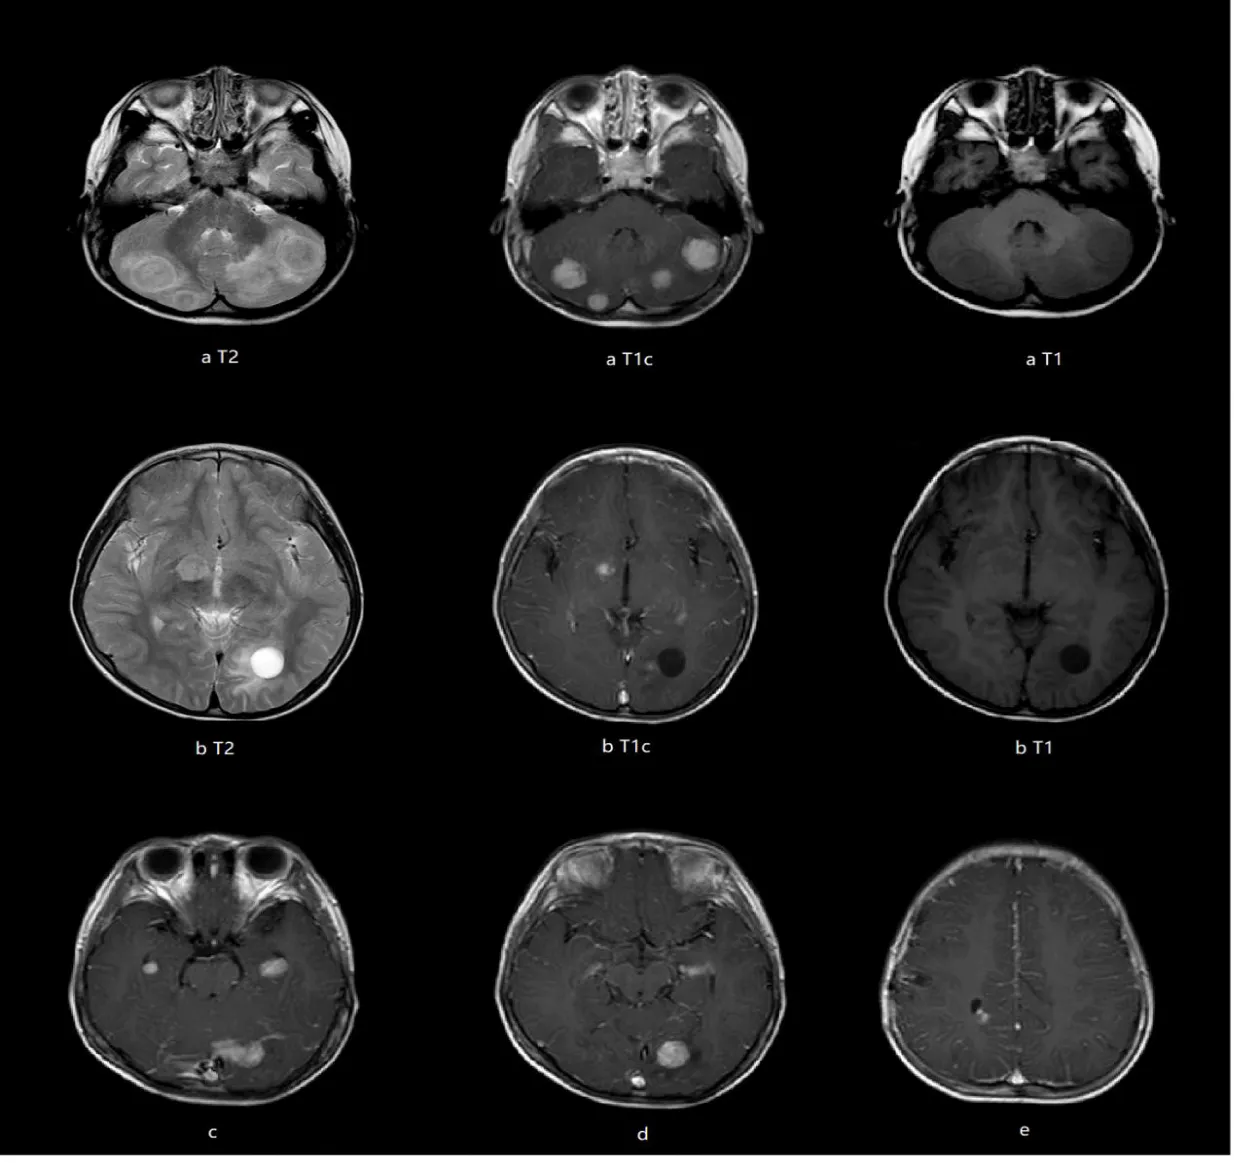

A previously healthy 4-year-old boy presented with a 2-year history of progressive left eye esotropia, without accompanying systemic symptoms such as headache, fever, or vomiting. His medical and family histories were unremarkable, with no exposure to contaminated water, undercooked meat, or pigeon feces. Neurological examination revealed subtle signs: slight limitation in left eye abduction and a positive Babinski sign on the left side. Initial laboratory tests showed normal hematologic parameters (WBC 7.76×10⁹/L, hemoglobin 130 g/L) and mildly elevated serum alkaline phosphatase (273 U/L) and calcium (2.31 mmol/L). Brain MRI demonstrated multiple heterogeneous lesions in bilateral cerebellar hemispheres, left occipital lobe, medial temporal lobes, right thalamus, and right frontal/parietal lobes. These lesions exhibited ring enhancement with perilesional edema and some with adjacent cystic components (Figures 1a-e).

Lumbar puncture under general anesthesia showed elevated CSF pressure (>330 mm H2O), lymphocytic pleocytosis (7×10⁶/L, 89% lymphocytes), and elevated protein (634 mg/L), though glucose levels were normal (2.7 mmol/L). Next-Generation Sequencing (NGS) of CSF identified Entamoeba dispar (447 reads), while extensive serological tests for bacterial, fungal, and parasitic pathogens (including tuberculosis, toxoplasmosis, and neurocysticercosis) were negative. Chest CT revealed subpleural and mid-lung field nodules (Figure 4), suggesting possible pulmonary involvement. The patient received three 10-day courses of metronidazole (50 mg/kg/day) over five months, with intervals of 1-2 months between courses. Follow-up MRI of 4 years showed progressive resolution of brain lesions, including absorption of the cysts, reduction of lesion size, decreased enhancement and alleviation of the perilesional edema (Figures 5a-e).

The imaging findings of this case revealed multiple nodular enhancing lesions, with cystic changes in some of the lesions. The Cerebrospinal Fluid (CSF) pressure was significantly elevated, with mild elevation of CSF protein levels, while the CSF glucose and chloride levels were essentially normal. The diagnosis of GAE was established through the detection of Entamoeba dispar sequences in the CSF by next-generation sequencing. Follow-up after treatment showed gradual reduction in the size of the lesions, which supports the correct diagnosis and effective treatment. This case has expanded our understanding of the pathogenic potential of Entamoeba dispar.